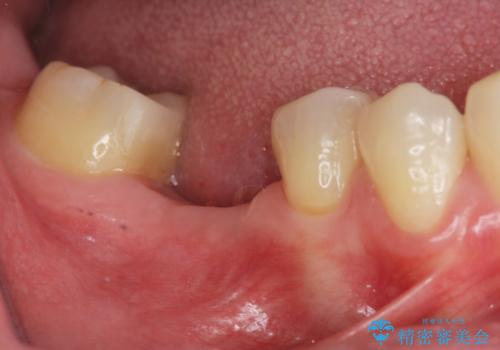

[ 臼歯部インプラント治療 ] 抜けた歯を治療したい

![[ 臼歯部インプラント治療 ] 抜けた歯を治療したいの症例 治療前](https://seimitsushinbi.jp/wp/wp-content/uploads/2022/06/b20681531f81bbbcb107d489675c3fe3-500x350.jpg?v=1655969039)